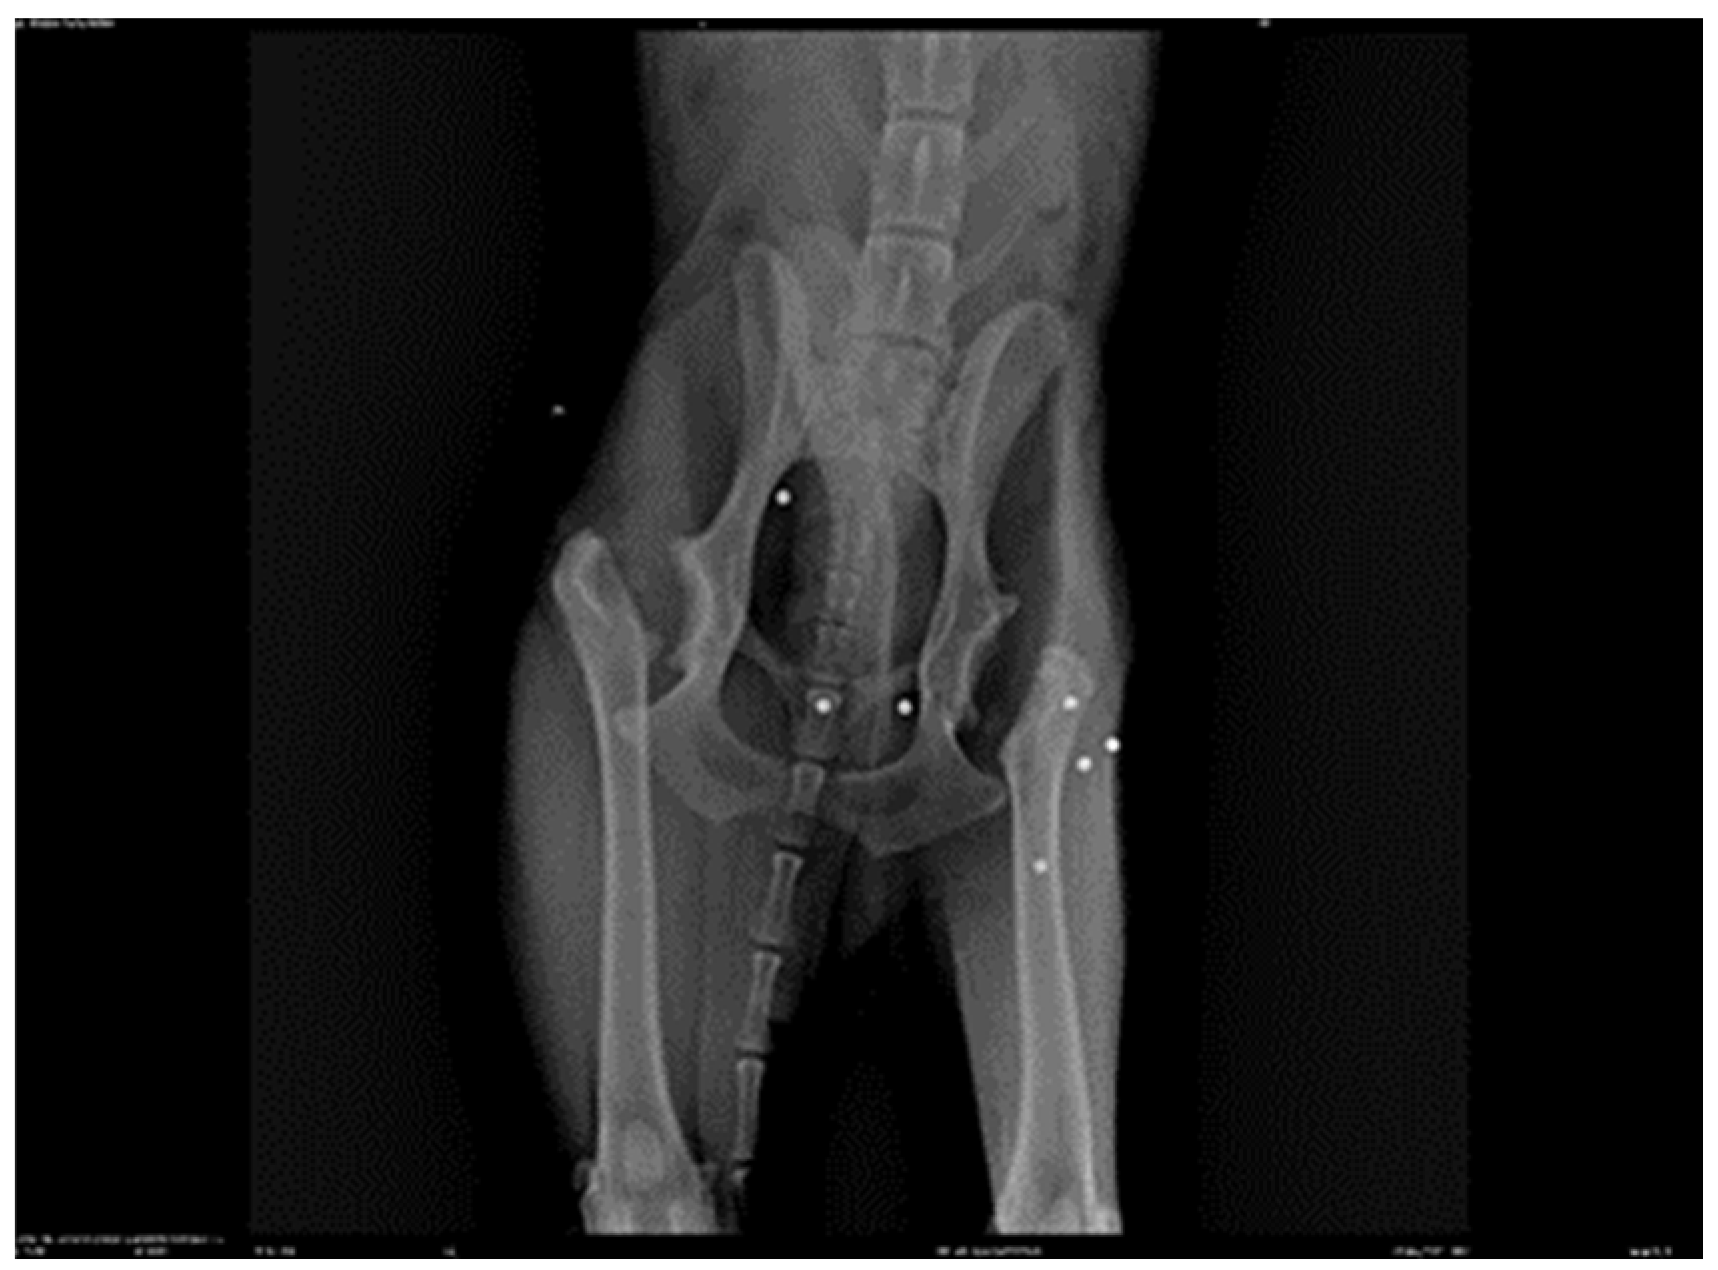

2.1. Patient Details a 7-Year-Old Male Canine Setter, 23 kg Was the Subject of This Study

2.3. Assessment

3. Results